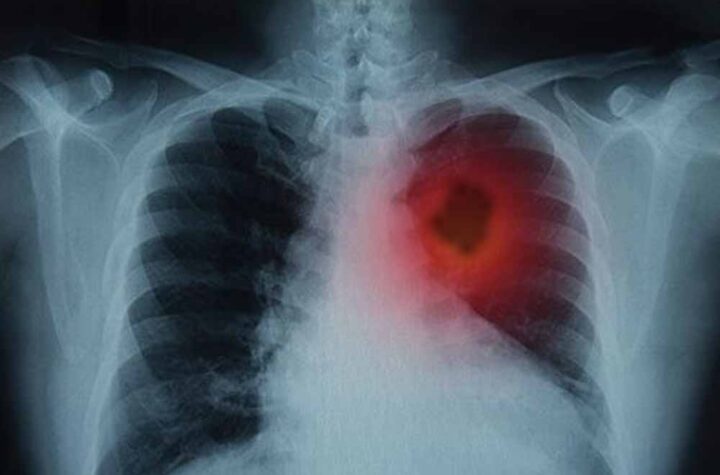

फेफड़ों के कैंसर से जूझ रहे लाखों लोगों के लिए विज्ञान की दुनिया से एक बहुत बड़ी और राहत भरी...